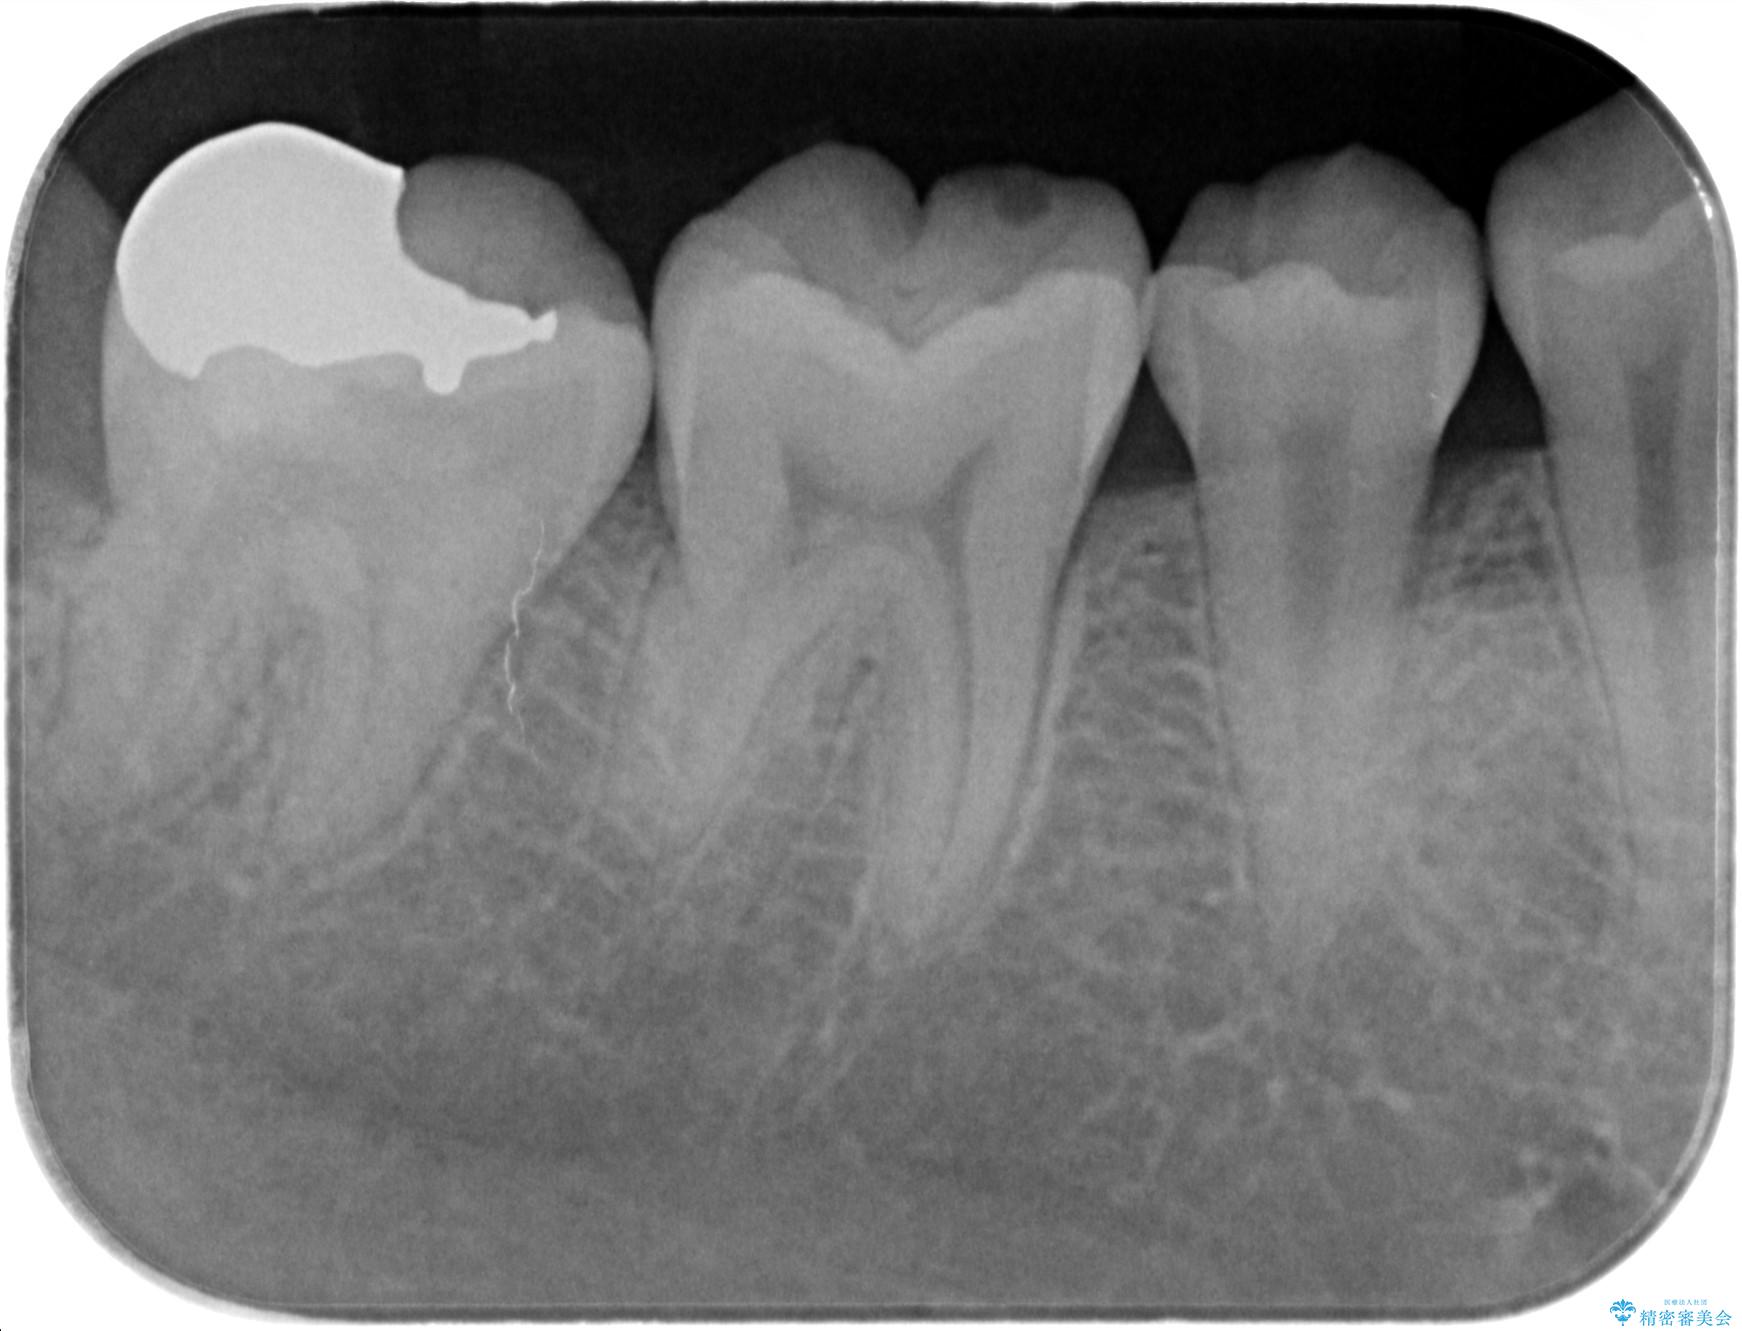

- 検査の結果虫歯が見つかった患者様です。

親知らずを抜歯してから虫歯を除去した後、ゴールドの詰め物で修復します。

比較的大きな虫歯でしたがゴールドでの修復にすることで歯の削る量を抑え、精度の高い治療を行うことができました。

親知らずの問題も同時に解決することで今後の虫歯リスクを抑えています。